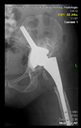

The radiological examination allowed us to verify the close bone-to-implant contact and the unchanged position of the implant during follow-up.

In all the cases operated with the above-described targeting procedure, the stems of the cups remained between the cortical bone surfaces without perforation of the linea terminalis, as shown by postoperative radiographs. There were no complicated surgical situations. In 16 cases, the wound healings were uneventful, and the hips were able to bear weight again after postoperative rehabilitation.